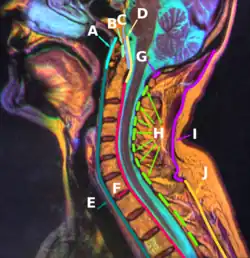

The ligamenta flava (sg.: ligamentum flavum, Latin for yellow ligament) are a series of ligaments that connect the ventral parts of the laminae of adjacent vertebrae. They help to preserve upright posture, preventing hyperflexion, and ensuring that the vertebral column straightens after flexion. Hypertrophy can cause spinal stenosis.

Each ligamentum flavum connects the laminae of two adjacent vertebrae.[2][3] They attach to the anterior portion of the upper lamina above, and the posterior portion of the lower lamina below.[1] They begin with the junction of the axis and third cervical vertebra, continuing down to the junction of the 5th lumbar vertebra and the sacrum.[2][3]

In the neck region the ligaments are thin, but broad and long; they are thicker in the thoracic region, and thickest in the lumbar region. They are thinnest between the atlas bone (C1) and the axis bone (C2), and may be absent in some people. They become longer inferiorly in the cervical spine, as the distance between adjacent laminae increases.[2]